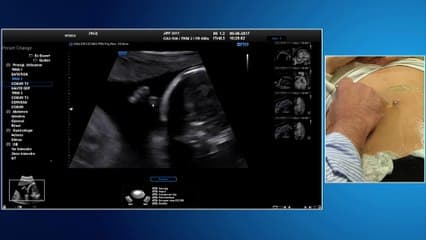

La plus grande ressource vidéo en échographie fœtale de France. Conférences, cours magistraux, démonstrations pratiques et podcasts par les experts du Collège Français d'Échographie Fœtale.

La médiathèque du Collège Français d'Échographie Fœtale (CFEF) constitue l'une des plus importantes collections de ressources vidéo dédiées à l'échographie fœtale en France. Avec plus de 3 261 vidéos, elle couvre l'ensemble des thématiques liées à la pratique échographique prénatale.

Vous y trouverez des conférences présentées lors des congrès nationaux et internationaux, des cours magistraux dispensés par des experts reconnus, des démonstrations pratiques sur des cas cliniques réels, ainsi que des podcasts et tables rondes sur les dernières avancées de la spécialité.